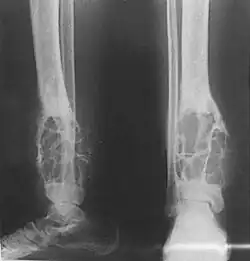

Se presenta predominantemente en huesos con localización subcutánea como la tibia. Por lo general los pacientes están en su segunda o tercera década de vida, aunque puede ocurrir en un rango bastante amplio de edad.